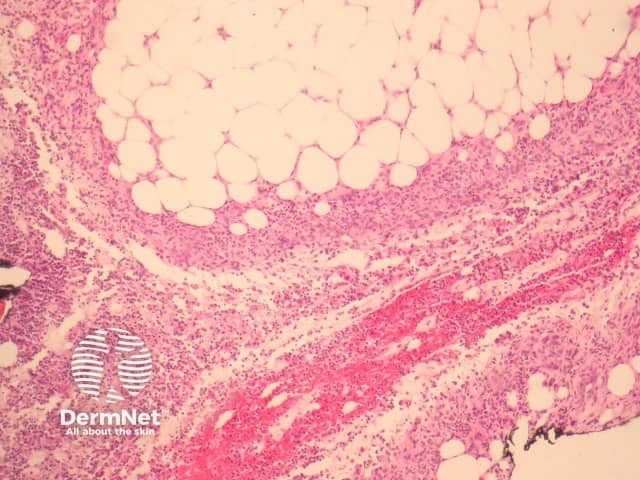

Histopathological examination usually reveals a lobular panniculitis but septal involvement may be seen. In early stages, neutrophils are interstitially arranged between collagen bundles of the deep reticular dermis, followed by a neutrophilic mixed panniculitis with lobular necrosis (figures 1, 2, 3). Vasculitis has been described in association with significant neutrophilic infiltration.

Figure 1